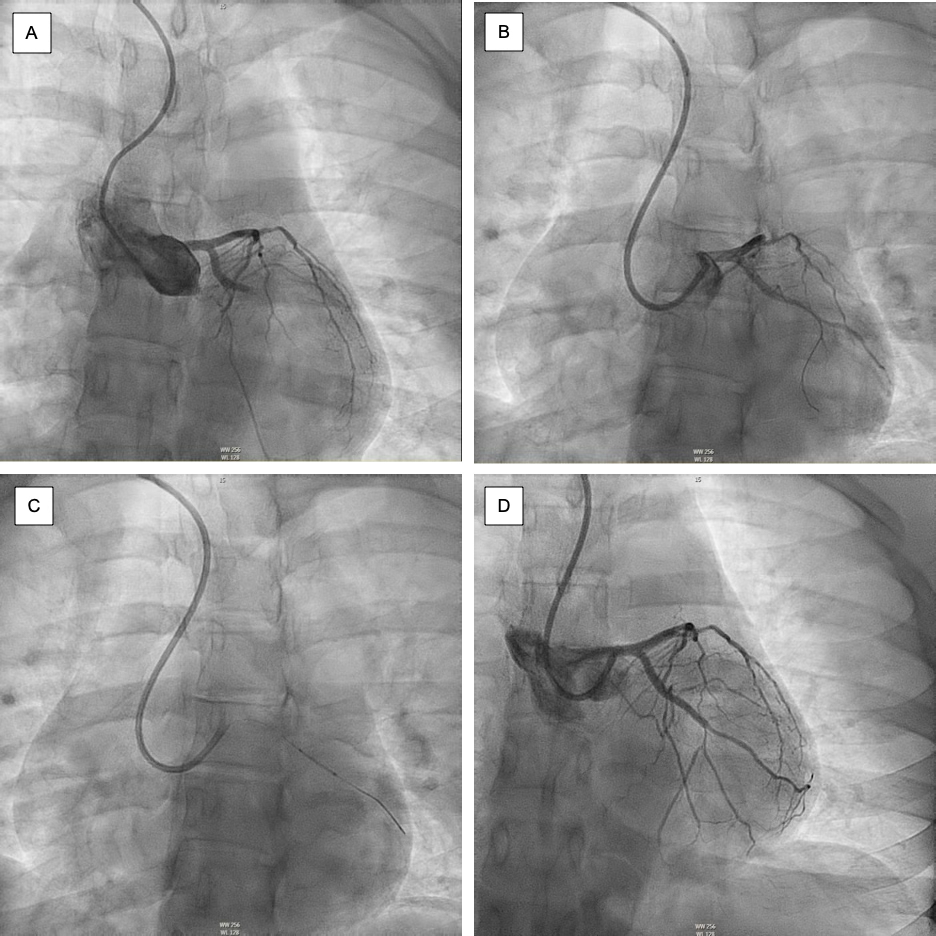

In the cardiac catheterization laboratory, the patient was found to have a total occlusion of the left circumflex coronary artery, as well as mild to moderate distal diffuse disease of the left anterior descending coronary artery. As demonstrated in Figure I, a balloon angiography was performed and a drug-eluting stent was placed in the left circumflex coronary artery, with resultant complete perfusion through the artery (TIMI 3 flow). After stent placement, the patient’s chest pain improved from a 10/10 to a 2/10. At the conclusion of the procedure, the patient was given ticagrelor and heparin, and taken to the Cardiac Care Unit (CCU).

Figure I:

Coronary angiography with percutaneous coronary intervention of the left circumflex coronary artery. (A) Angiogram showing 100% occlusion of left circumflex coronary artery. (B) Advancement of the guidewire. (C) Positioning of the stent. (D) Post-stenting TIMI-3 flow in the culprit vessel.